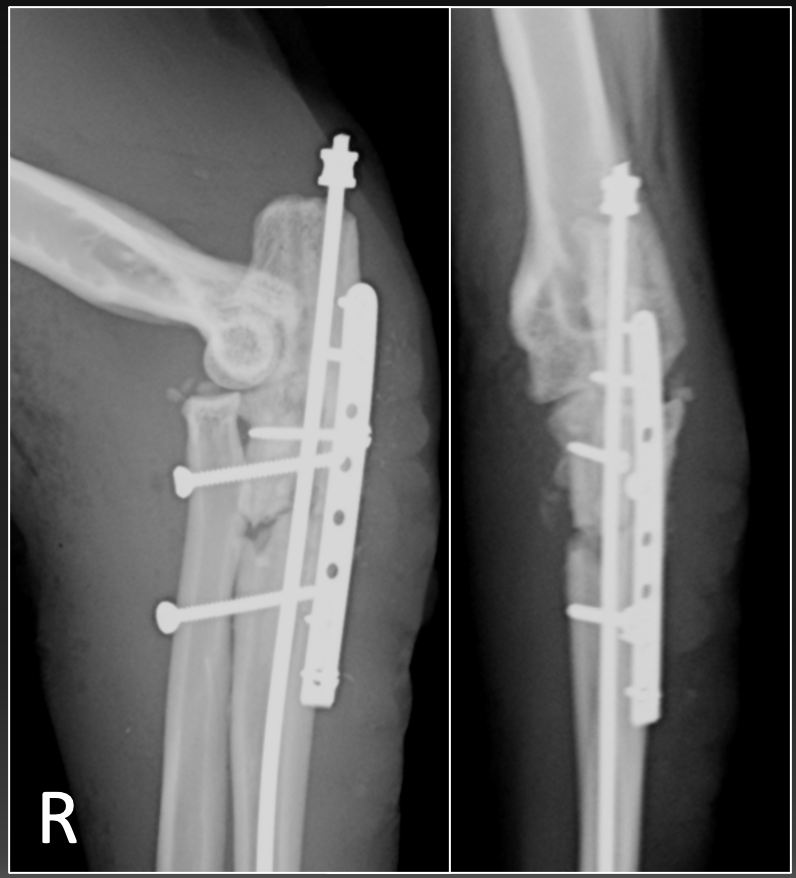

治療は、ギプスなどの外固定と呼ばれる方法も選択肢の一つですが、この状態でバンテージなどで完治させることは困難であり、外科手術を実施しました。手術では髄内ピンと呼ばれるピンを挿入後、プレートにて骨片を固定しました。また、橈骨と尺骨がずれないように、スクリューを打ち込みました。

術後は段階的に、まずはスクリューを抜去し、その後骨が癒合したため、スクリューを抜去しました。プレートのスクリュー抜去時には骨は癒合し、一本の骨になってくれているのがわかると思います。また、症状も改善し、通常通りジャンプして生活できるようになっていました。